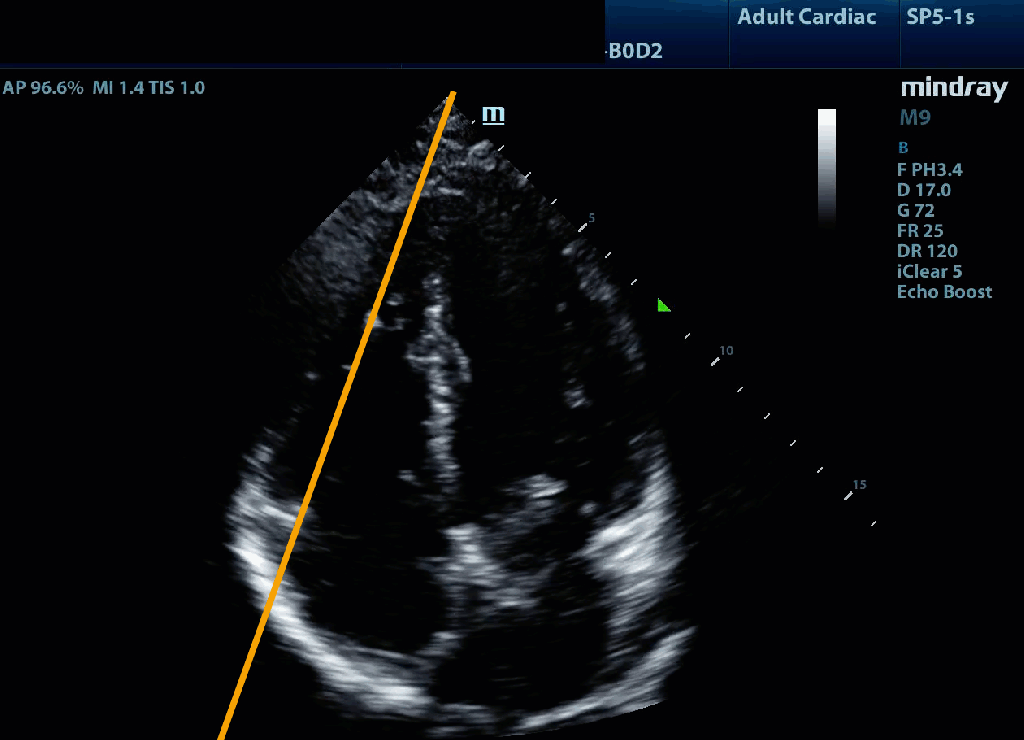

Measuring TAPSE involves aligning an M-mode line with tricuspid annulus in the A4C and measuring the longitudinal movement of the annulus toward the apex from end diastole (the valley) to peak systole (the peak). TAPSE <17 mm is consistent with impaired RV function.

Practically, we support a qualitative approach where the question is geared toward identifying severe impairment; i.e. does the tricuspid annulus seem to move vigorously and around 2 cm by the depth markers toward the apex (image on the left below) or is there minimal longitudinal translation (as shown in the image on the right).